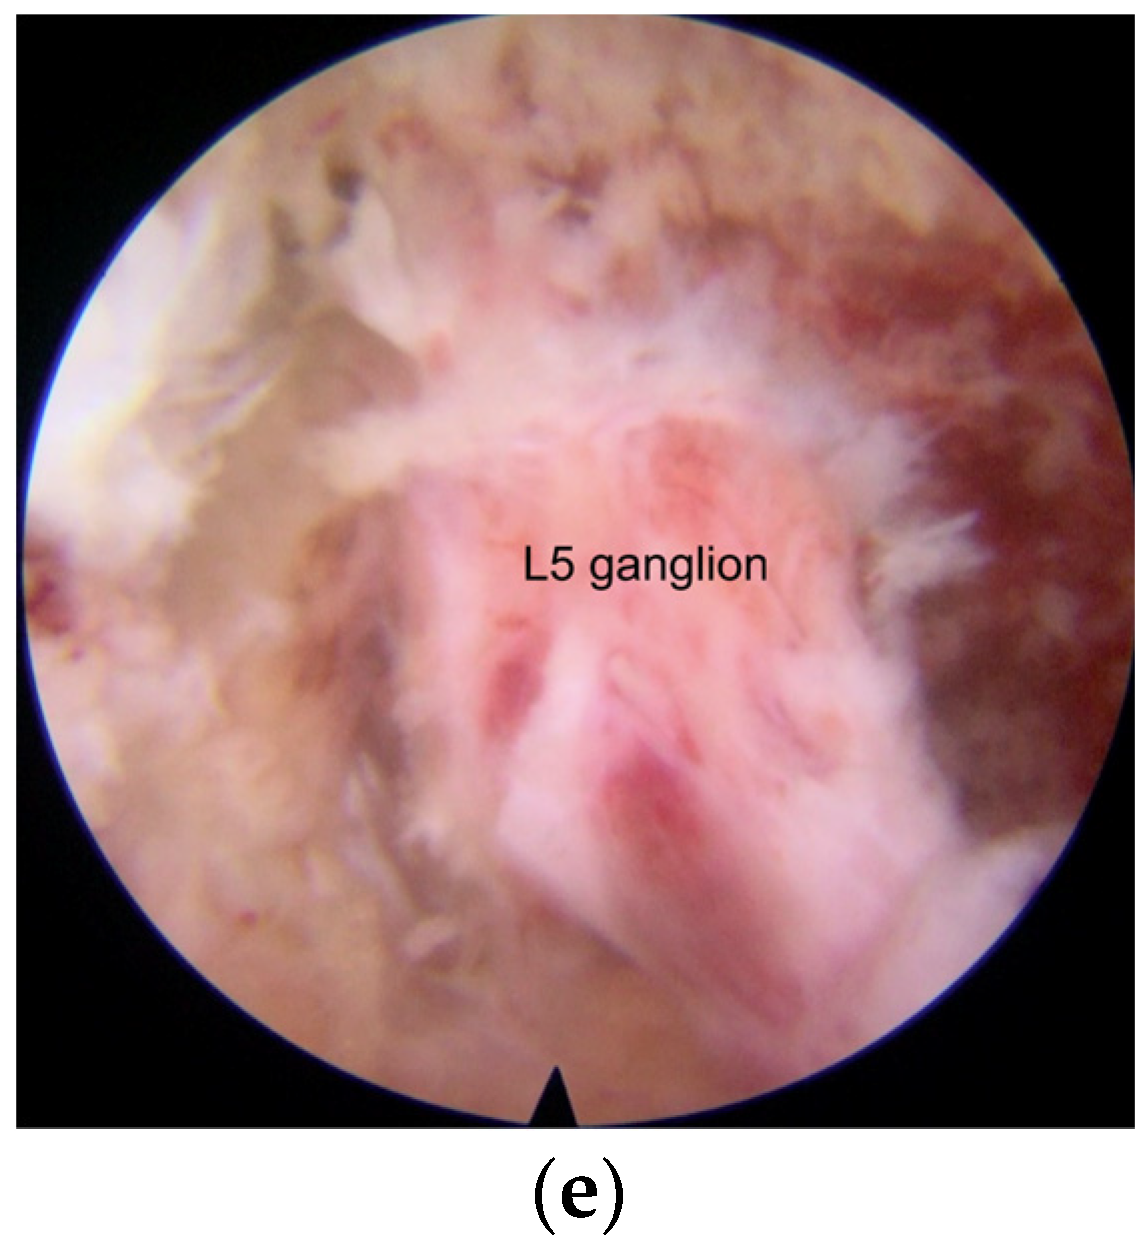

- Under the endoscopic view, the structure of the foramen can be seen more clearly. Smaller operating instruments used in endoscopic operation can avoid irritating DRG.

- The modified interlaminar approach we used can show an almost parallel trajectory to the L5 nerve root in the foramen and provide excellent visualization of the nerve root all along its course without the need for significant retraction. This technique was called “no touch decompression” [36], as FS can be treated without more retraction of DRG compared with that via transforaminal approach, especially in complicated cases and L5-S1 cases with anatomical limitations [37].

- Dissecting scar tissue from bone rather than nerve tissue is an effective method to reduce the risk of dural tear [42]. Bone tissue at the lateral and dorsal sides of the nerve structure was treated after the tip of the trephine, and anatomical landmarks were identified in X-ray view. The unscarred virgin tissue can be easily viewed and entered by endoscopic. Therefore, the operation can be safely performed without excessive retraction of the dura, nerve root, and DRG, which may be tethered at the foramen, and dissection of the scar tissues surrounding the nerve structure.

- The entry direction of the instrument is not toward the nerve root and dural sac. The operation in the spinal canal is far from the dural sac and nerve root, and the operation in the intervertebral foramen is parallel to the nerve root. It reduces the risk of dural tear and neural injury.